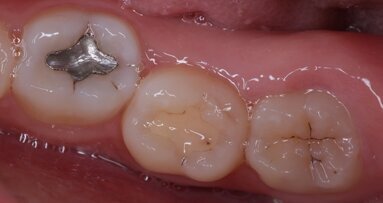

WHITE OAK, Md., U.S.: The U.S. Food and Drug Administration (FDA) has updated its guidance for the use of dental amalgam in tooth restorations. The agency said in September that the use of dental amalgam should be avoided whenever possible in certain groups, such as in pregnant women, women who are planning to become pregnant, in children and in people with certain preexisting neurological diseases.

The use of dental amalgam has remained widespread in the U.S., despite its use being phased out or banned in certain groups in a number of countries. Until its recent announcement, the FDA had considered dental amalgam restorations to be safe for adults and children over the age of 6.

As detailed in its September statement, the FDA’s new position on the use of dental amalgam is that its use may pose a greater risk for potential harmful health effects for certain groups, and it therefore recommends that its use in these groups be avoided “whenever possible and appropriate”.